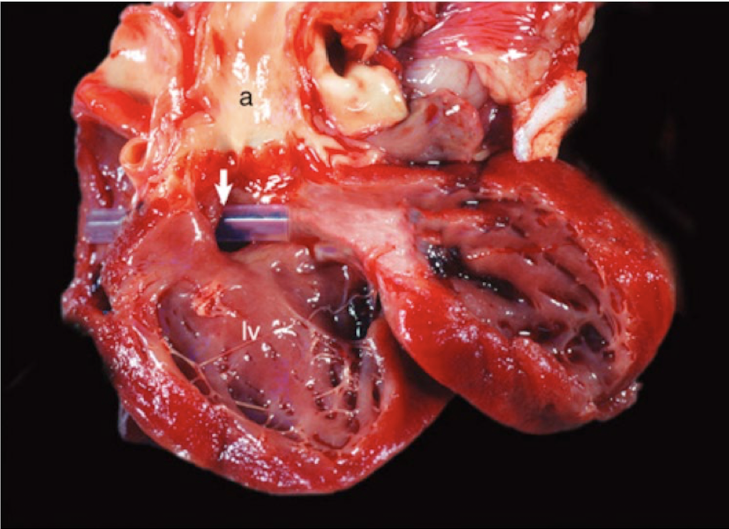

<p>What is this showing?</p>

What is this showing?

ventricular septal defect

high and low ventricular septal defect